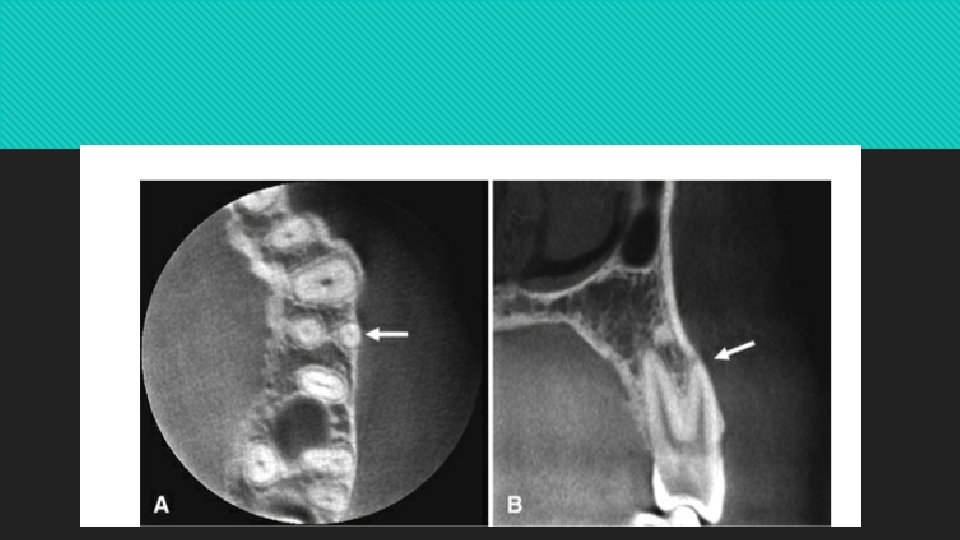

CBCT scans portray the three-dimensional morphology of the roots, pulp chambers, and pulp canals more accurately than intraoral radiographs

Individual canals are best identified on axial sections the length of the root and its exit through the apex are typically assessed on coronal and sagittal sections

In a mature tooth, the shape of the pulp chamber and canal may change. A gradual deposition of secondary dentin occurs with aging. This process begins apically, proceeds coronally, and may lead to pulp obliteration.

Trauma to the tooth (e. g. , from caries, a blow, restorations, attrition, or erosion) also may stimulate dentin production, leading to a reduction in size of the pulp chamber and canals.